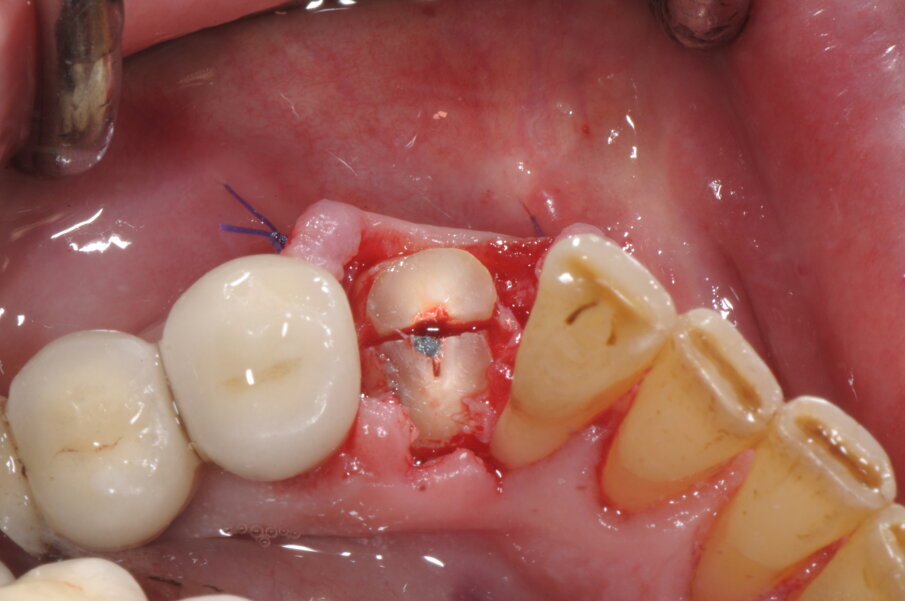

Il caso clinico che andremo a descrivere vede interessata una paziente di anni 69, di sesso femminile, in buona salute, non fumatrice, con frattura del 4.3 ricostruito in precedenza con una ricostruzione diretta in resina composita dopo trattamento endodontico. In accordo con la paziente abbiamo elaborato un piano di trattamento che prevedeva l’estrazione della porzione radicolare residua del canino inferiore di destra, l’inserimento simultaneo di un impianto osteointegrato e un carico protesico immediato. In anestesia locale è stata praticata un’incisione intrasulculare, con minimo scollamento dei tessuti molli, per accedere alla superficie di frattura (Fig. 1). La procedura chirurgica, valutato lo spessore ridotto della corticale vestibolare in accordo con i protocolli PIEZOSURGERY applicati alle estrazioni, ha previsto la regolarizzazione della linea di frattura apicalmente alla giunzione amelo-cementizia, mediante un inserto OT7 e, successivamente, un frazionamento radicolare in direzione mesio-distale con inserto OT7S-3 (Figg. 2, 3).

Fig. 2

Fig. 3

Questa separazione determina la creazione di uno spazio di manovra all’interno dell’alveolo che favorisce la lussazione, con leva manuale, della radice senza determinare compressioni a carico delle superfici alveolari, specie quella corticalizzata vestibolare, poco elastica e di scarso spessore (Figg. 4, 5; Vercellotti, 2016). Dopo accurata detersione dell’alveolo residuo integro, grazie all’effetto cavitazione della soluzione fisiologica, si è proceduto all’allestimento del sito implantare attraverso una tecnica di preparazione combinata che vede l’utilizzo sia di frese a spirale che inserti PIEZOSURGERY. In questo protocollo chirurgico di preparazione endo-alveolare del sito implantare gli inserti PIEZOSURGERY permettono con facilità la perforazione ossea e l’allestimento del sito seguendo un asse differente rispetto a quello dell’alveolo residuo, allo scopo di ricercare la maggiore stabilità primaria possibile dell’impianto (pur mantenendo un adeguato profilo di emergenza protesico).

Fig. 4

Fig. 5